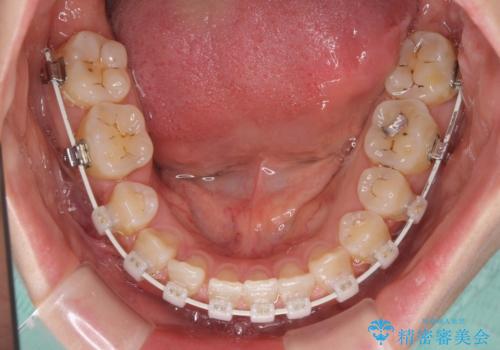

- 矯正装置

- 審美装置

- 治療期間

- 2年9ヶ月